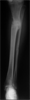

Treatment - Ilizarov Lengthening

Feb 98

Mar 98

Apr 98

Jun 98

Post

Op

LIMB LENGTH

• From ASIS to MM

▪ Right - 76cm

▪ Left – 75.5cm